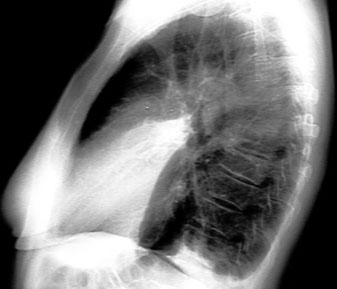

- Density in the projection of lingula in lateral view

- Air bronchogram in lateral

- No significant loss of lung volume